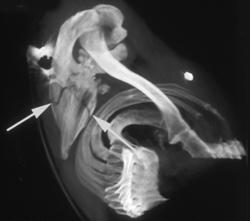

Myositis Ossifications With Fusion